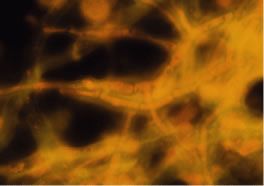

The preferred stains for identification of hyphal fragments and yeasts in smears of corneal scrapings are acridine orange and calcofluor white.33, 34, 35, 36, 37, 38 Each of these techniques requires use of a fluorescent microscope. The optical activity of acridine orange is due to the binding of the dye to deoxyribonucleic acid (DNA) of bacteria, fungi, and amoebae to form a green-fluorescing complex. Acridine orange is more sensitive than the Gram stain in detecting microorganisms in clinical specimens36 and is, therefore, a rapid and sensitive method for screening all corneal smears in suspected infectious keratitis. If microorganisms are detected by acridine orange stain, the slide can be washed and stained with Gram or other specific stains. The preferred procedure is to fix the smears in 95% methanol for 5 to 10 minutes, apply the acridine orange dye (number 3336-75)* for 2 minutes, rinse the slide with tap water, blot dry, and examine by fluorescent microscopy. Hyphal fragments stain yellow-orange or green, and yeasts stain brilliant orange (Fig. 22).

Fig. 22. Curvularia senagalensis keratitis. Fluorescent microscopy. Direct smear of corneal scraping stained with acridine orange. Note the distinction of the septate hyphal fragments. (× 630.)

Calcofluor white is a fabric whitener used in the textile industry. The material absorbs ultraviolet light at 340 to 400 nm and emits a blue light. Calcofluor white has an affinity for cellulose and chitin, which are common compounds of hyphal fragments and yeasts.37,38 The preferred procedure is to fix the smear in 95% methanol for 5 to 10 minutes, apply calcofluor white stain (number 17353)* to the surface of the slide, apply a coverslip over the slide, drain excessive fluid with an absorbent towel, and examine by fluorescent microscopy. Depending on the selection of filters, fungal elements stain apple green to steel gray against a rust or red background (Fig. 23).

Fig. 23. Curvularia senagalensis keratitis. Fluorescent microscopy. Direct smear of corneal scraping stained with calcofluor white stain. Prominent septate hyphal fragments are noted. (× 160.)